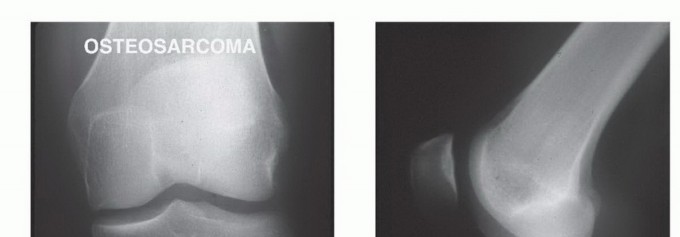

BACKGROUND Ralph C. Marcove (Memorial Sloan Kettering Cancer Center) and Kenneth C. Francis (New York Univers…